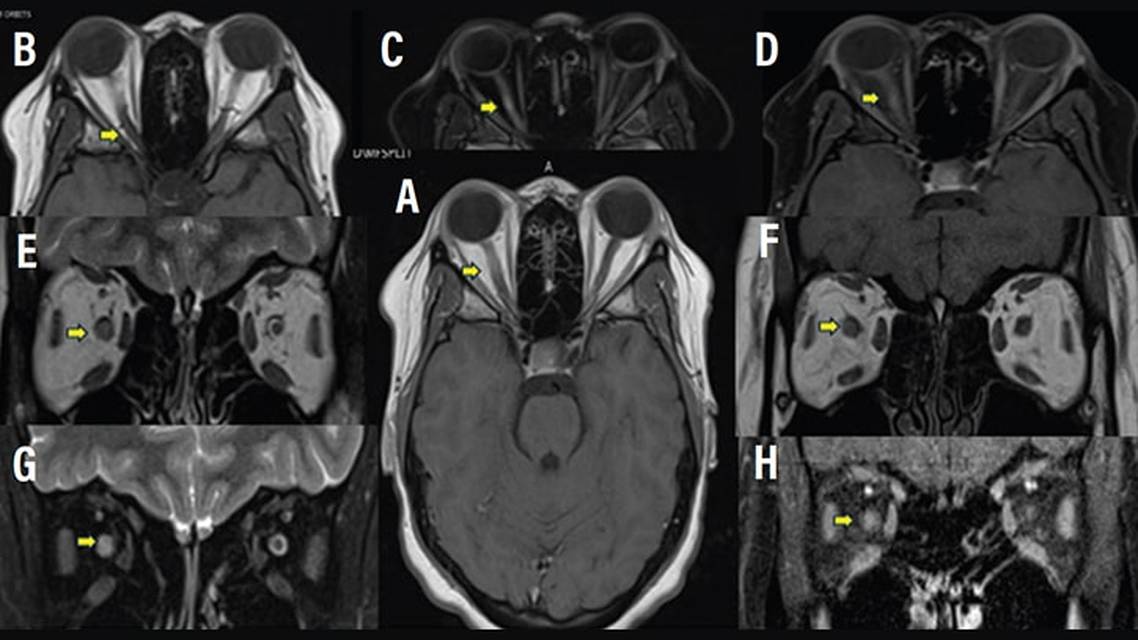

MRI remains a cornerstone in the diagnosis and management of MS. Based on the ONTT, people with ON but no brain lesions have a 16% risk of progression to MS compared with 51% in those with increasing brain lesions within 5 years.7 Although optic nerve imaging was once considered secondary, advances in high-resolution, fat-suppressed orbital MRI have led to enhanced lesion detection, even in early ON stages, increasing the specificity for diagnosis.8,11 These dedicated orbital images demonstrate characteristic gadolinium-enhanced lesions on postcontrast T1-weighted imaging or increased signal in T2-weighted spin-echo neuroimaging within the optic nerve with patterns for ON in MS that differentiate it from other conditions (eg, NMOSD, MOGAD).8,11 MS-associated ON frequently shows ≥1 focal short, non–longitudinally extensive segments of hyperintense signal on T2-weighted images, which indicates anterior optic nerve inflammation and edema, typically sparing the posterior nerve, chiasm, and perineural tissue. These findings differentiate MS from NMOSD and MOGAD. Figure 1 includes an overview of features of ON in MS.1-5,9,12 Findings associated with acute ON tend to resolve over time. As such, orbital MRI may not detect asymptomatic optic nerve lesions, which limits the utility of MRI for the evaluation of DIS in the outpatient setting and highlights the need for alternative testing.8,11,13